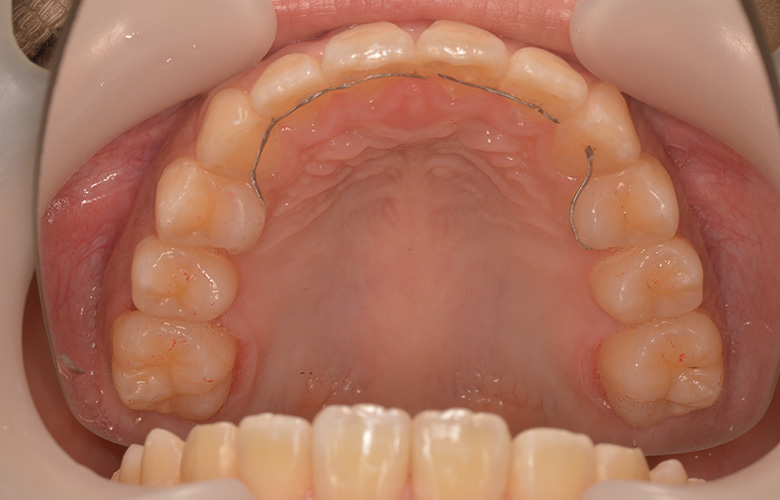

上顎

3D装置を主体とした治療法(3Dテクニック)を用いて、歯茎の土手(歯列弓)自体を広げることで、自然な形で歯列を整えることに成功。歯を抜かないので、噛む力を弱めることもありません。